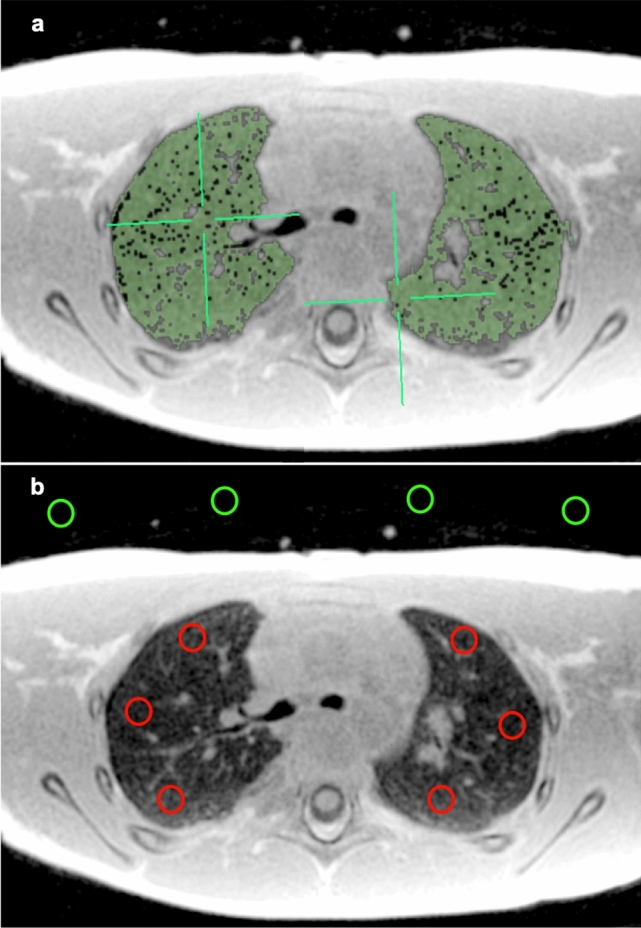

The right and left lungs were manually segmented by signal intensity thresholding avoiding high intensity vessels, and average signal values were extracted (Fig. 1). Lung segmentation was performed using the open-source image analysis software Osirix MD version 11.03 (Pixmeo Sarl 2016, Bernex, Switzerland). Four two-dimensional regions-of-interest (size of 20 mm2 each) were drawn in the air anterior to the patients’ thorax in each slice and the average background signal intensity was extracted (Fig. 1). One additional two-dimensional region-of-interest of variable size was drawn inside the trachea on an axial slice at the carina level to measure the signal intensity of the air column within the trachea. In addition, two-dimensional regions-of-interest (size of 20 mm2 each) were positioned in the anterior, middle, and posterior anatomical regions of each lung, for both sequences at the level of the carina in the patients with normal lung parenchyma (Fig. 1). The regions-of-interest did not include any high intensity vessels to avoid signal contamination. Finally, the average signal of both lungs was used to determine the whole lung signal intensity while the average anterior signal intensity (respectively middle and posterior) was determined by the average signal of the anterior region-of-interest of both lungs (respectively middle and posterior regions-of-interest).

Fig. 1.

Manual lung segmentation by thresholding and region-of-interest placement of a 6-year-old female subject. a Axial slice showing the manual segmentation of lung parenchyma (green). b Axial slice with background (green) and lung (red) regions-of-interest